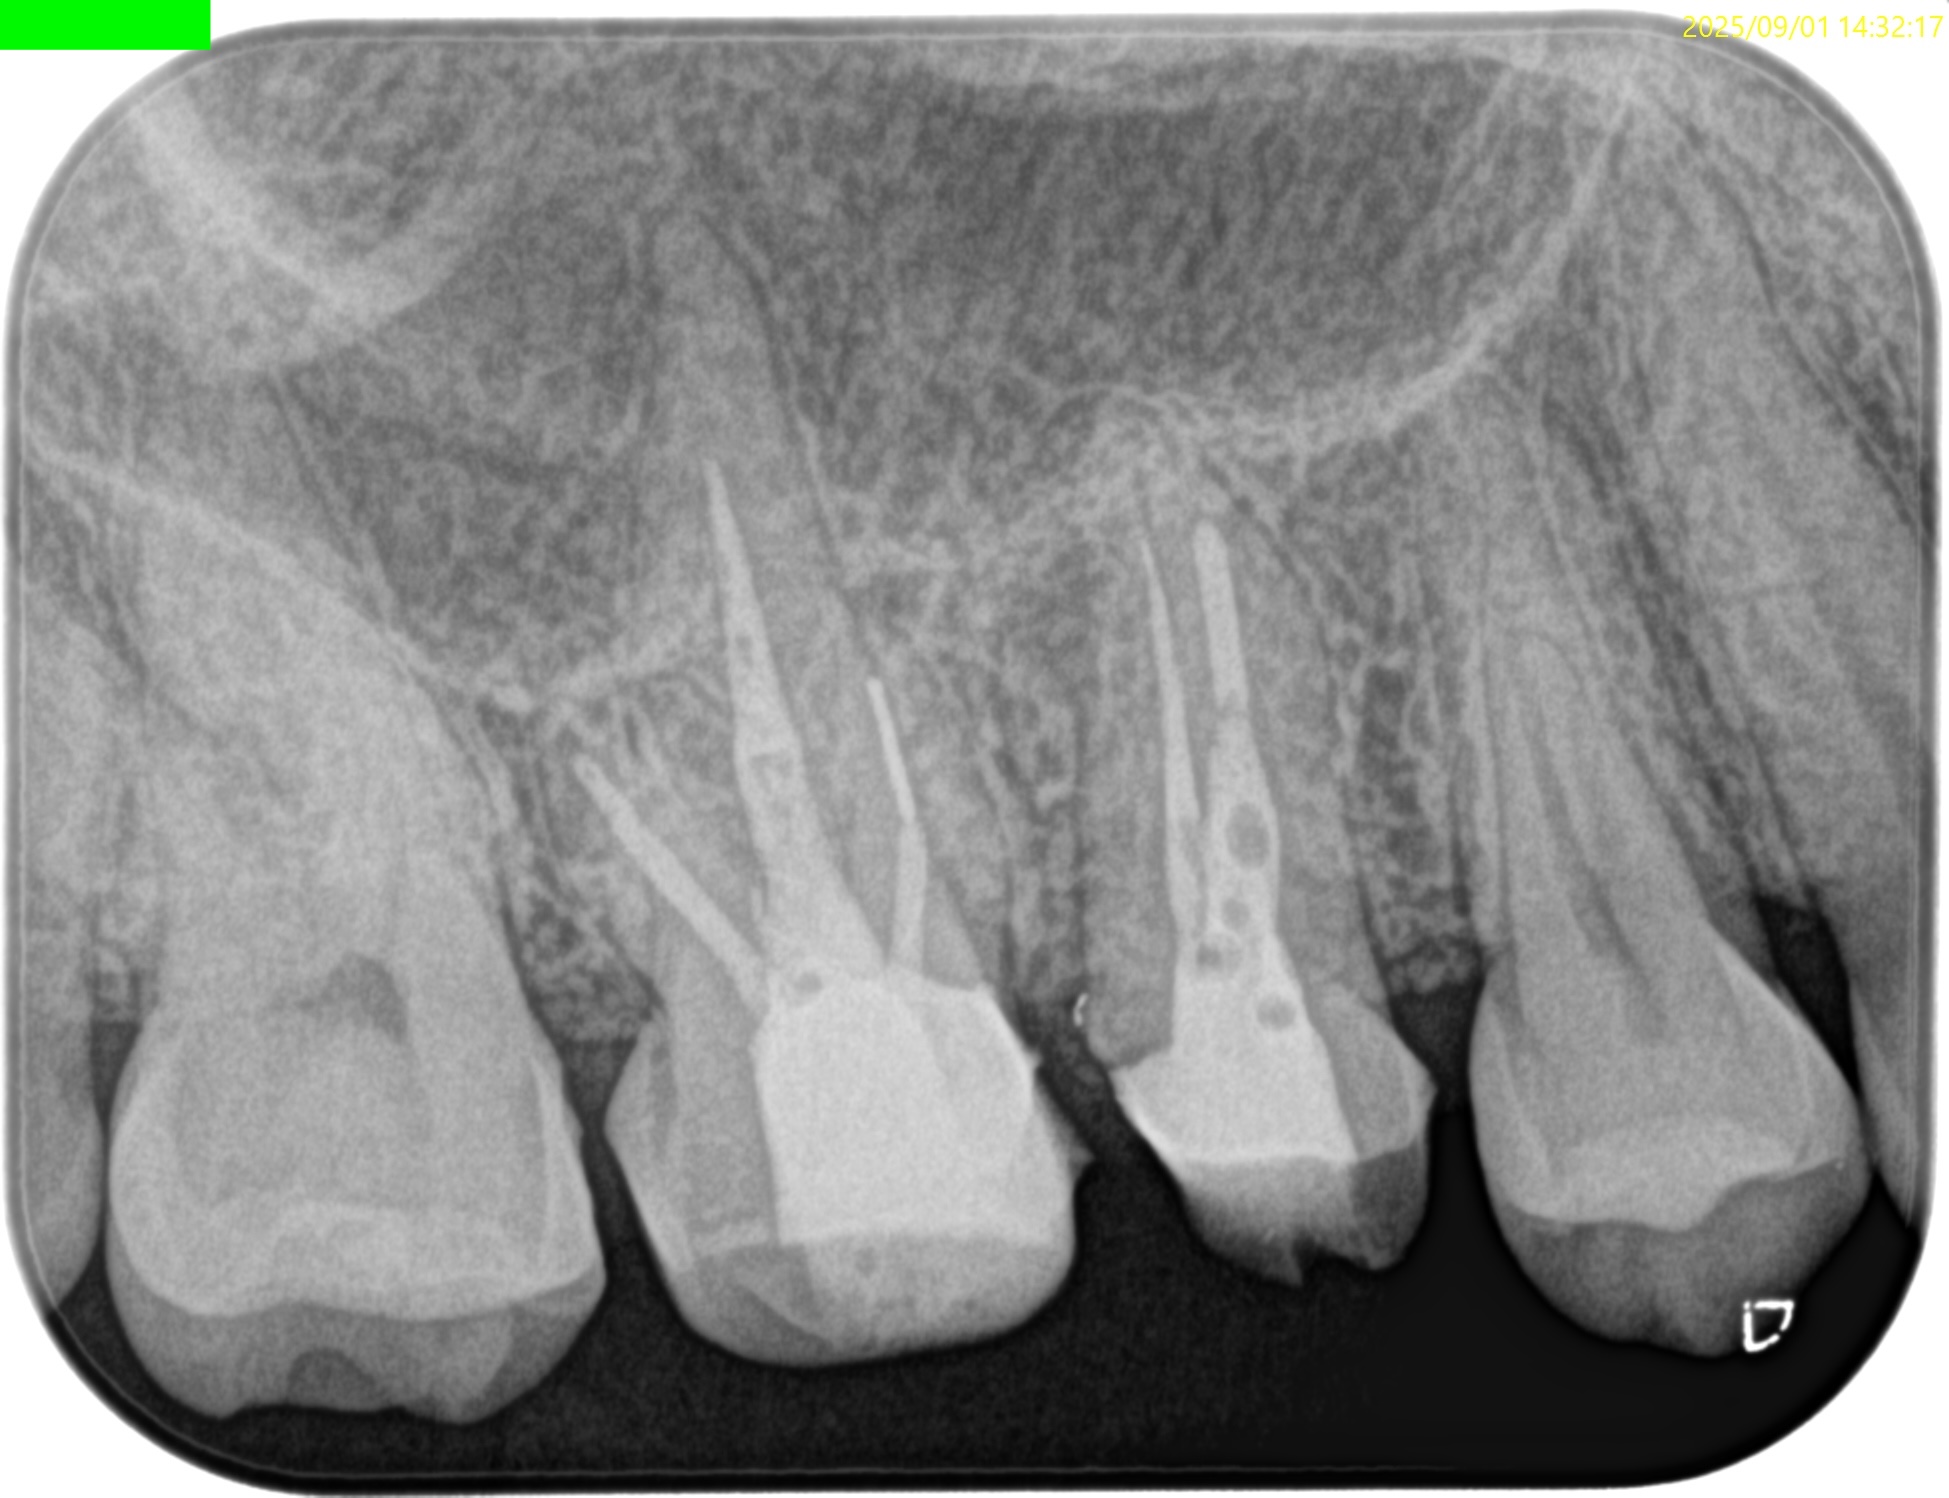

#3 MB Apicoectomy(2025.10.22)

CEJよりも10mm下方の#3 MBのApexをOsteotomyで探索する。

このApexから4mmの部分を想定しRoot resectionした。

今回は折れたFileごとMBのApexを除去した形だ。

この後メチレンブルーで染めて逆根管形成した。

逆根管充填した。

術後にPA, CBCTを撮影した。

問題はないだろう。